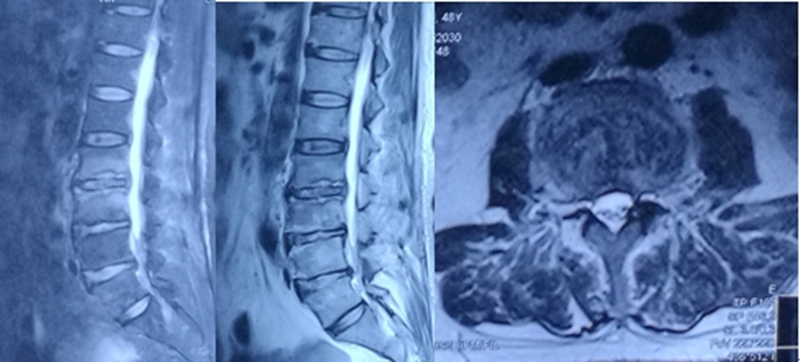

6、术后椎间隙感染

术后椎间隙感染发生率约为1-5%,虽发生率较低,但有可能引发严重后果。患者主要症状可为相关节段腰痛,与活动有关,严重者静卧时也会出现腰痛,同时伴有发热,相关炎症指标升高。可能与穿刺针位置不佳穿破肠管、穿刺过程中带入椎间盘外部皮肤组织、术中无菌操作不严格、反复穿刺等有关。

其病情发展较快,但是根据患者体征、血象及影像学检查可较早发现,发现后应立即使用广谱抗生素治疗,必要时可进行穿刺活检,确定病原菌的类别,以应用敏感抗生素,若效果不佳可考虑手术治疗(开放处理及内镜处理均有文献报道),其治疗过程较长,在多次复查炎症指标均正常后可停用抗生素。对于椎间隙感染预防是关键。穿刺不可进入腹腔,避免长时间/频繁的手术操作。